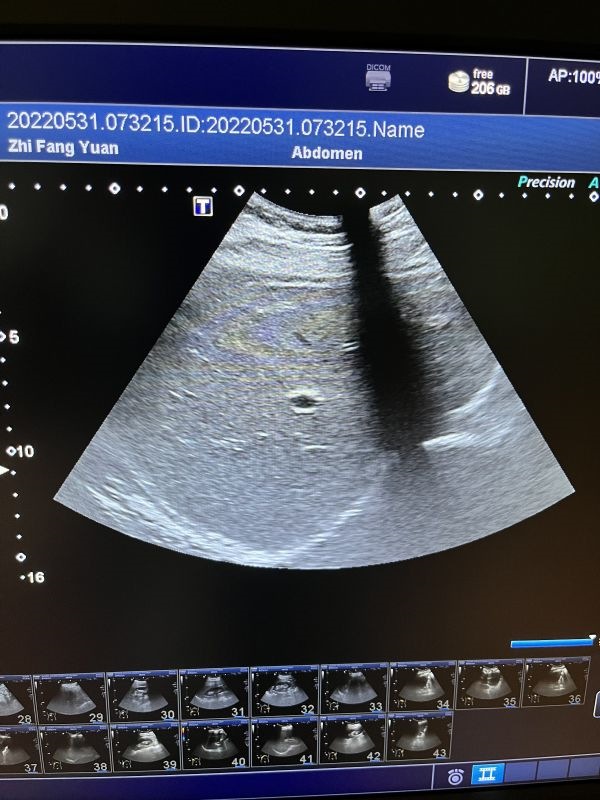

更换声头,更换外壳。上机后图像正常。